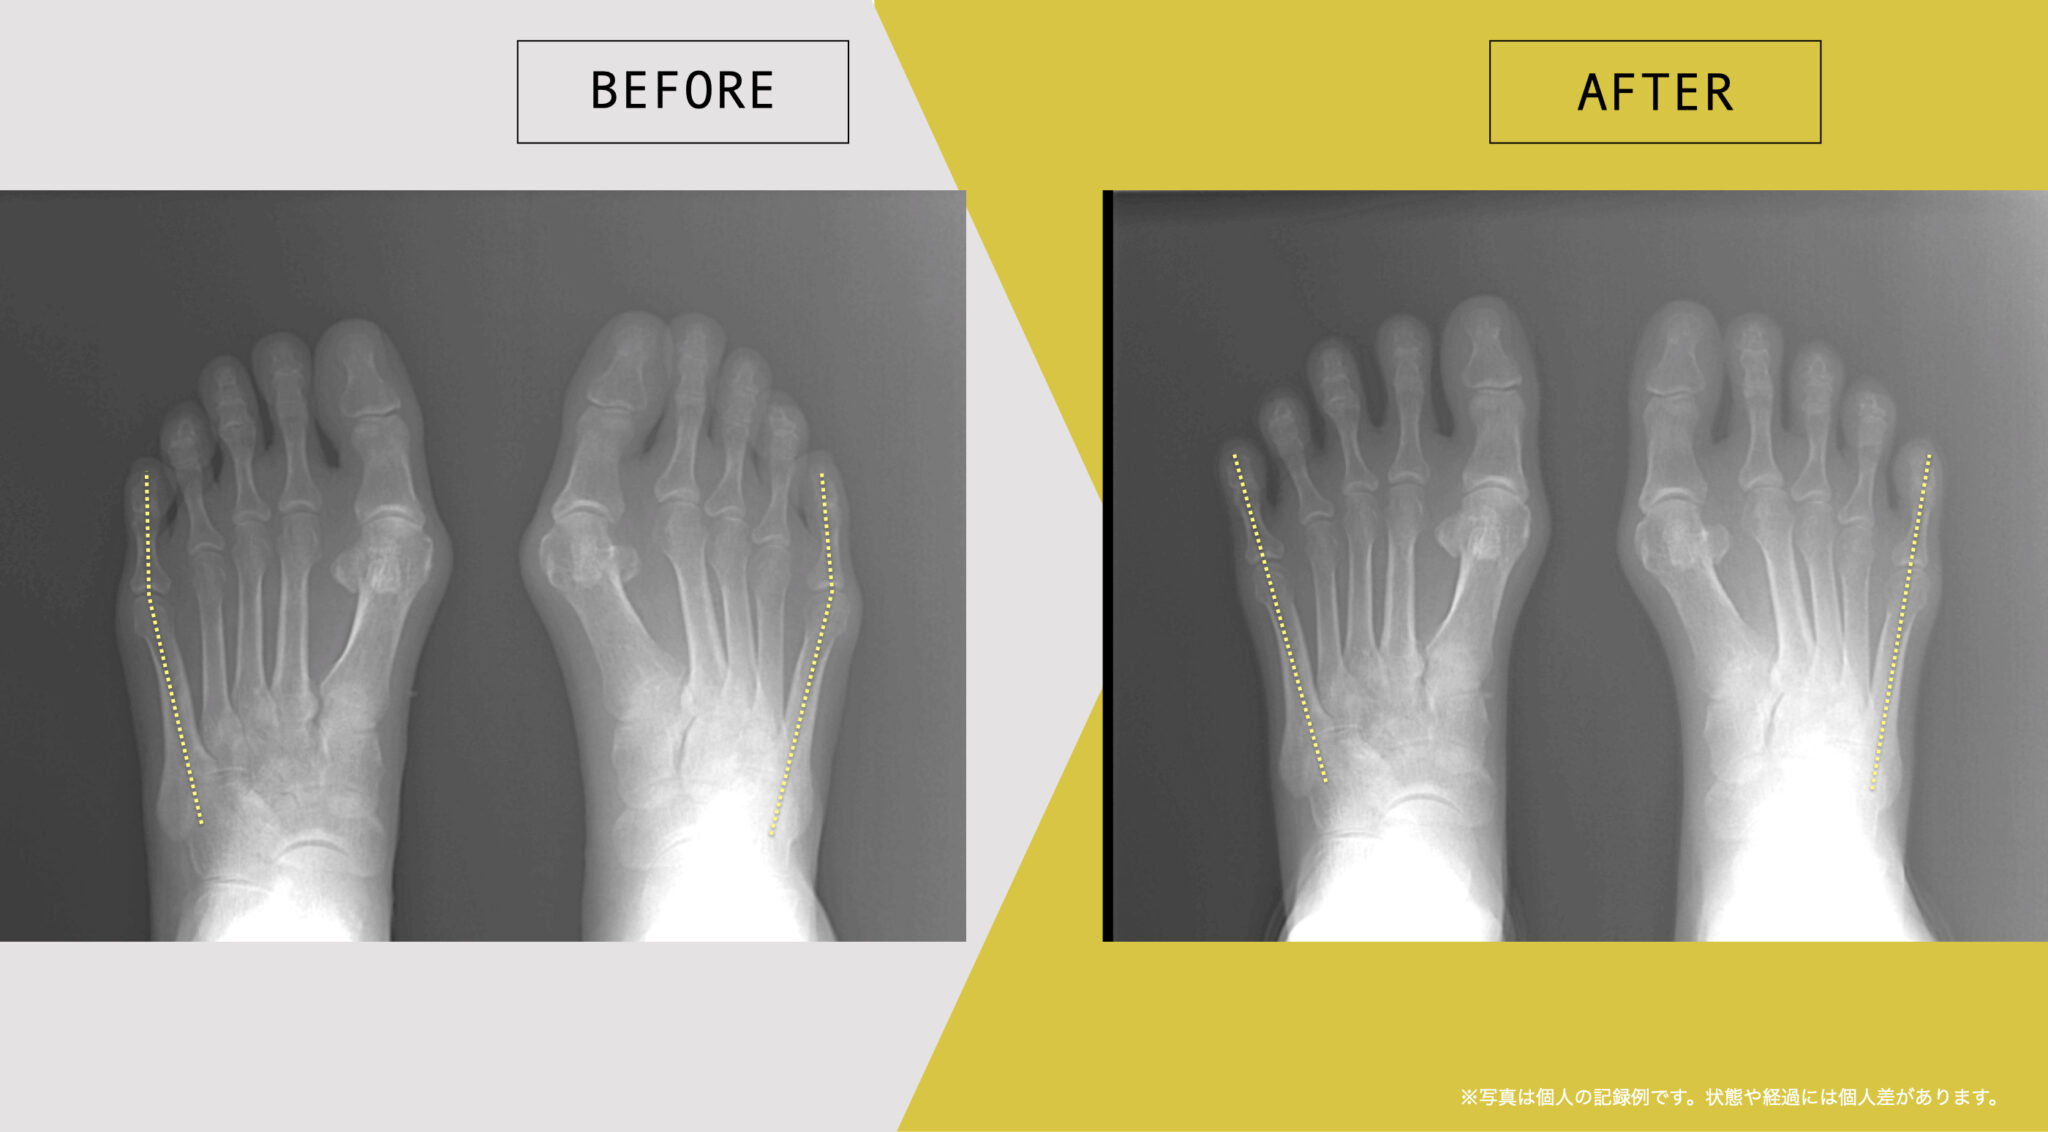

東京大学名誉教授・石井直方先生(運動生理学)とともに、2020〜2022年に行った共同研究では、YOSHIRO SOCKSの着用および、ひろのば体操を日常的に実践された方を対象に、内反小趾などに関する足指の状態や角度の変化について評価を行いました。

内反小趾角

開始時の内反小趾角は25.1°

8週間後の内反小趾角は5.3°

8週間目の平均値では、開始時と比べて、内反小趾角に19.8°の変化がみられました。

※開始前と8週間目の平均値の差

※グラフは臨床試験における平均値の推移を示したものです

※結果には個人差があり、すべての方に同様の変化が生じるわけではありません

※本データは石井直方名誉教授(東京大学)の助言を得て実施された研究に基づくものです